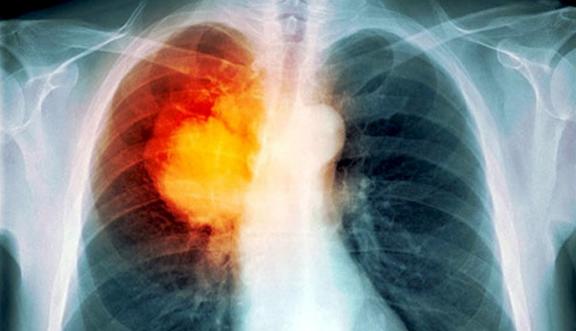

肺癌等於得了絕症!沒想到只要天天做

肺癌等於得了絕症!沒想到只要天天做 觀看人數:434